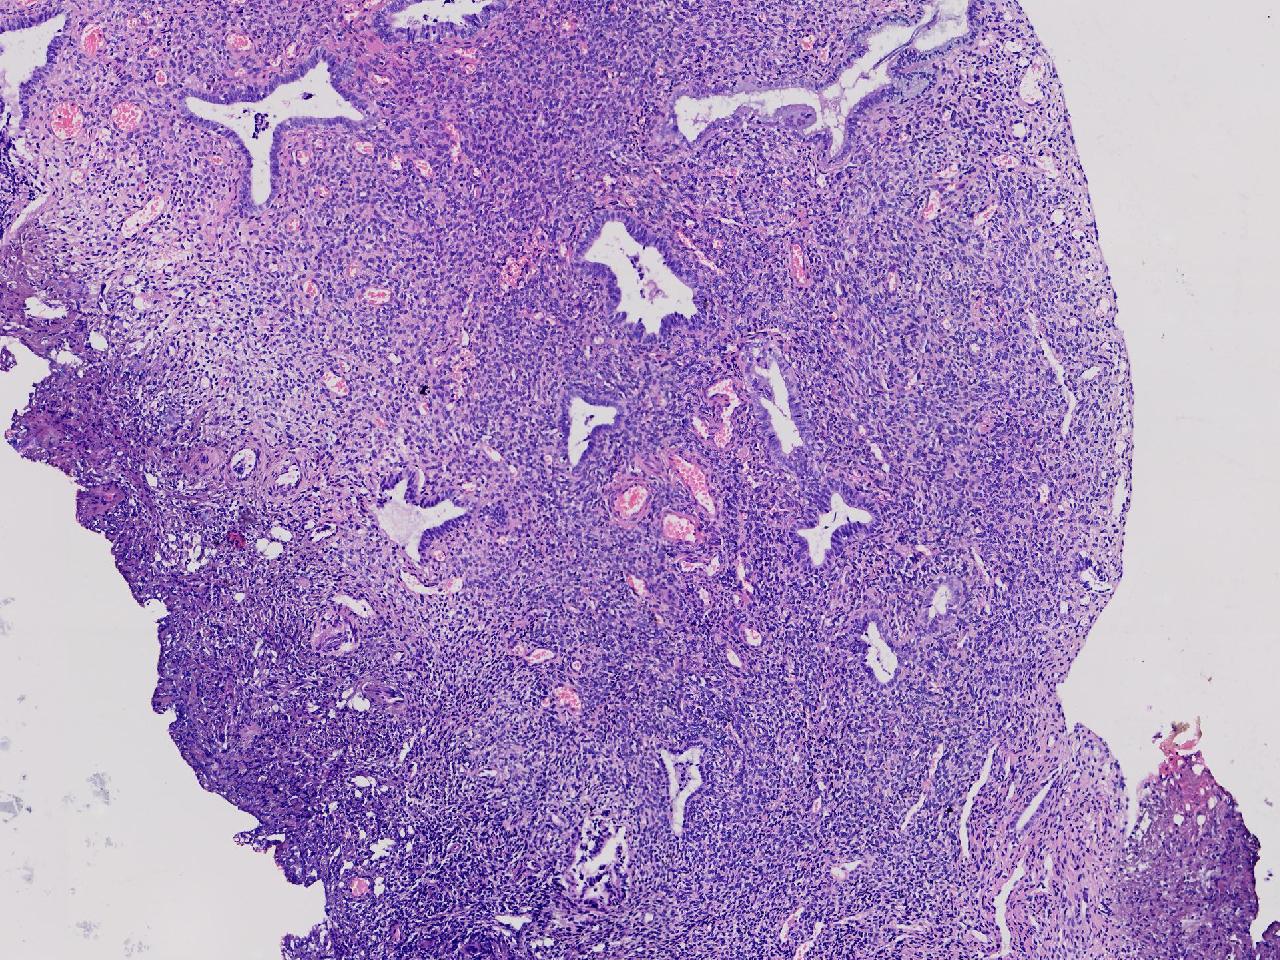

性别

女

年龄

56岁

彩超示宫腔内见5x3ml的团状偏强回声结节,边界清。

宫腔息肉?

灰粉色不整形软组织多块,0.5X0.3X0.3厘米。

首先考虑子宫内膜息肉,有些区域间质细胞较密,找找看有没有核分裂。

彩超提示强声团体积不小,待完整切除送检再综合诊断。